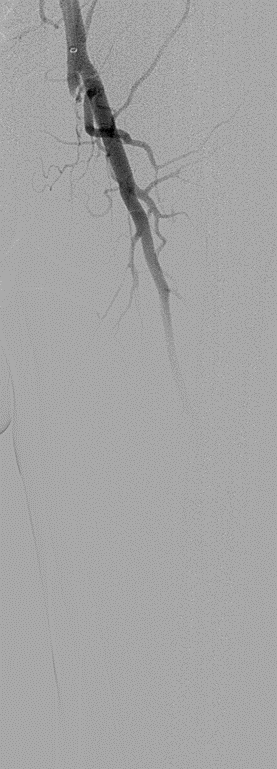

开通:以内膜下技术为主,逆穿是常用且有效的辅助手段。

预扩:充分预扩张至关重要,需逐级使用高压球囊,最终达到 6mm 直径,以获得足够的管腔。

支架植入:遵循“由远及近”原则,先放置远端 DES,再覆盖中段 VB,最后处理近端。利用 Eluvia 的可调节性优化重叠。

后扩:常规使用 6mm 高压球囊进行后扩张,确保支架充分贴壁和管腔获得。

用药:术中术后必须充分抗凝,推荐“双通道”抗栓方案(如利伐沙班+阿司匹林),以模拟 bypass 的血流动力学效果。